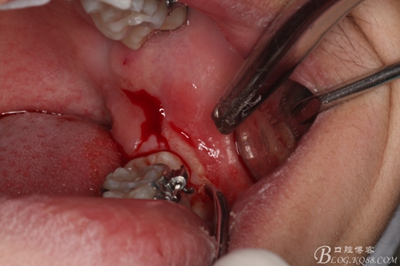

圖4.局部下牙槽神經(jīng)無(wú)痛阻滯麻醉

4_副本.jpg

圖5.行遠(yuǎn)中水平切口+37近中垂直切口

5_副本.jpg